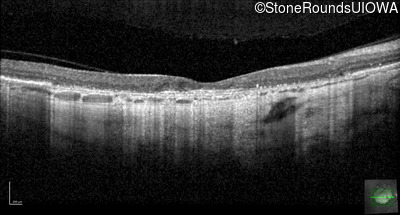

Optical Coherence Tomography - Left - 10/200

Exemplar / OCT Stack